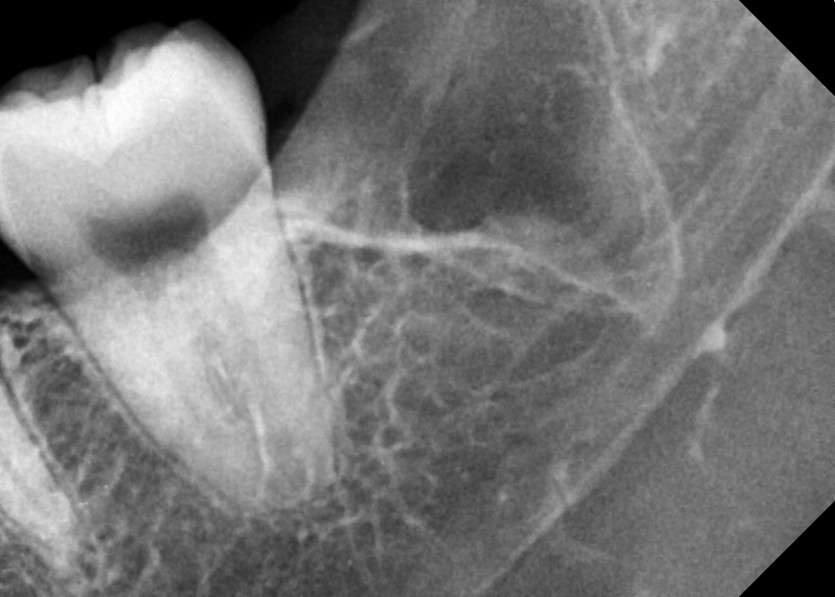

#18,28,38,48 사랑니 발치

구강 외과 전문의가 당일 발치했습니다.